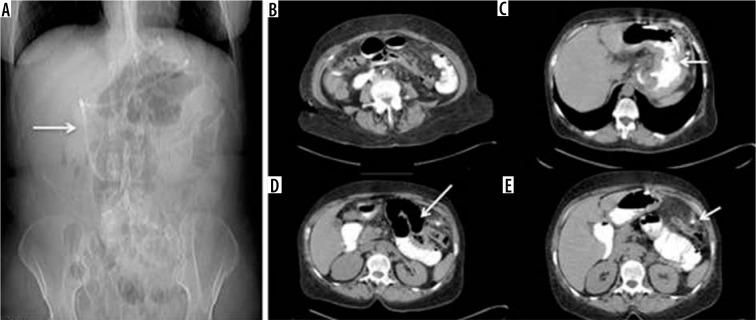

诊断性影像学在减重手术急性并发症诊断中的应用

Diagnostic imaging in the diagnosis of acute complications of bariatric surgery.

The aim of study is to identify the frequency of acute complications and imaging findings at gastro-intestinal transit (GI) and computerised tomography (CT) in a group of obese patients who developed clinical suspicion of acute complications (painful and meteoric abdomen, nausea, vomiting, fever, intestinal blockage) in post bariatric surgery.

MATERIAL AND METHODS

We retrospectively review 954 obese patients who underwent bariatric surgery between 2013 and 2019. The study included 72 patients who developed clinical suspicion of acute complications (painful and meteoric abdomen, nausea, vomiting, fever, intestinal blockage) within 6 days of bariatric surgery of sleeve gastrectomy, gastric banding, gastric bypass with Roux loop confirmed by CT, and who underwent a gastrointestinal transit before the CT examination.

RESULTS

GI exam allowed visualisation of 58% of complications. Analysing the data for each surgical technique, 46 post-operative complications were found involve gastric banding. The most frequent was bandage migration (26 cases, 56 %), identified in all cases at GI transit and then confirmed on CT.

CONCLUSIONS

The study suggests that CT should be used to clarify all doubtful or clinically discordant GI transit exam results. The participation of a radiologist in qualification and post-operative evaluation is important for bariatric surgery patients.

本研究旨在确定一组肥胖患者在接受减重手术后出现急性并发症临床疑似症状(腹痛、腹胀、恶心、呕吐、发热、肠梗阻)时,胃肠道造影(GI)和计算机断层扫描(CT)检查中急性并发症的发生率及影像学表现。

材料与方法

我们回顾性分析了2013年至2019年间接受减重手术的954例肥胖患者。该研究纳入了72例在袖状胃切除术、胃束带术、Roux袢胃旁路术后6天内出现急性并发症临床疑似症状(腹痛、腹胀、恶心、呕吐、发热、肠梗阻)且经CT证实,并在CT检查前进行了胃肠道造影的患者。

结果

GI检查能够发现58%的并发症。分析每种手术技术的数据,发现46例术后并发症与胃束带术有关。最常见的是束带移位(26例,56%),所有病例在GI造影时均被发现,随后经CT证实。

结论

该研究表明,对于所有可疑或临床结果不一致的GI造影检查结果,均应使用CT进行明确。放射科医生参与减重手术患者的术前评估和术后评估非常重要。